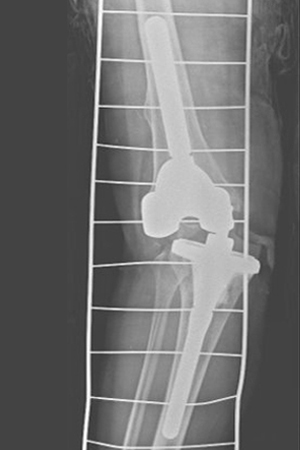

인공관절치환술은 관절염이나 특정 질환 또는 외상에 의하여 무릎이 더 이상 제 기능을 하지 못해 관절의 일부분을 제거하고 인체공학적으로 제작된 기계를 삽입해서 관절의 운동 기능을 회복시켜주고 통증을 없애는 수술입니다. 인공관절 수술을 통해서 운동 범위를 향상 시킬 수 있습니다.

인공관절치환술은 관절염이 발생된 부분만 인공관절로 바꿔주고 정상적인 나머지 무릎관절은 그대로 무릎 기능을 유지할 수 있도록 하는 반치환술과 심하게 관절염이 있는 경우 모든 관절 조직을 제거하고 인공관절을 삽입하는 전치환술로 나뉩니다. 환자의 연골 상태에 따라 인공관절 반치환술, 전치환술을 시행합니다.

사고, 손상, 불완전한 기기, 체질적 요소 등으로 인공관절 재수술이 있을 수 있습니다. 매우 드문 수술이지만 고난도 스킬이 필요한 수술이 인공관절 재수술 입니다. 인공관절 재수술도 잘하는 병원은 인공관절 수술도 잘합니다.

인공관절 전치환술 시행

인공관절재수술 시행